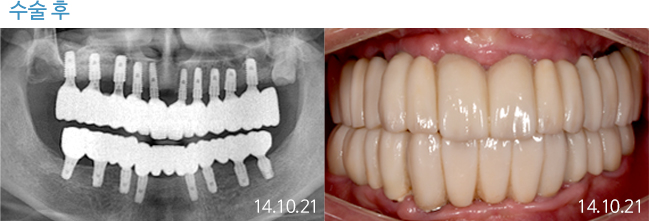

한 번 잘 심으면 10년 뒤에도 끄떡없는

더와이즈 임플란트

첨단 장비를 이용한 정확한 진단, 안정성이 입증된 정품 재료 사용,

노하우가 풍부한 숙련된 의료진의 시술 등이 임플란트 수명을 결정합니다.

※ 실제 본원에서 치료 받은 환자의 동의를 얻어 게재했습니다.

개인의 특성에 따라 부작용이 발생할 수 있으므로 담당의와 충분히 상의하시길 바랍니다.